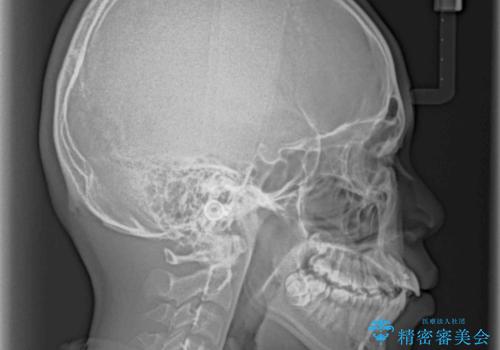

膨らんだ口元 ワイヤー装置での抜歯矯正

- 口元の突出感を気にして来院された患者様です。

上下前歯が著しく前突している状態であったので、上下左右の第1小臼歯4本を抜歯し、ワイヤー装置にて矯正治療を行うこととしました。

舌の突出癖により、前突になったと考えられたため、舌のトレーニングをしっかりと行うよう指導しました。

小学生の頃に上顎前歯をぶつけ、歯の一部が破損している状態であったので、歯根が歯槽骨と癒着して移動しない可能性がありましたが、無事に治療を終えることができました。